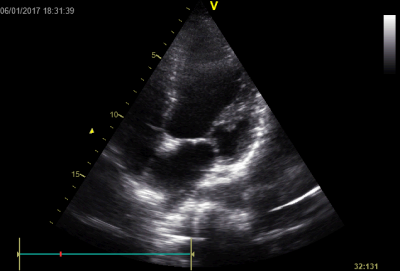

Video 1 - Akutní koronarografie prokázala normální nález na věnčitých tepnách s výjimkou suspekce na lehký spasmus na pravé koronární tepně.Echokardiograficky byla zjištěna těžká dysfunkce dilatované levé komory s nezvětšenou pravou komorou (video 2).

Na kůži byl nápadný, v čase proměnlivý hnědočervený makulopapulózní exantém s převahou na předních a laterálních partiích stehen a na podbřišku, pro který byla nemocná vyšetřována již v minulosti bez jasného výsledku. Koncentrace tryptázy v séru v kontrolních odběrech byla překvapivě zvýšena nadále i v odstupu několika dnů (tabulka 2), ačkoliv při anafylaxi jsou hodnoty zvýšeny pouze v období do čtyř až šesti hodin. Vzhledem k suspektnímu dermatologickému nálezu, který imponoval jako urticaria pigmentosa, a ke zvýšení bazální tryptázy padlo podezření na systémovou mastocytózu. Zahájili jsme proto příslušnou léčbu antihistaminiky (levocetirizin). Stav se postupně zlepšoval a šestý den hospitalizace jsme pacientku extubovali, nedošlo k poškození mozku (cerebral performance category scale 1 [CPC-1]) a při současné terapii milrinonem se zlepšila i ejekční frakce levé komory z 25 % na 55 % (video 2–4); dobrá funkce levé komory přetrvávala i po vysazení inotropik.